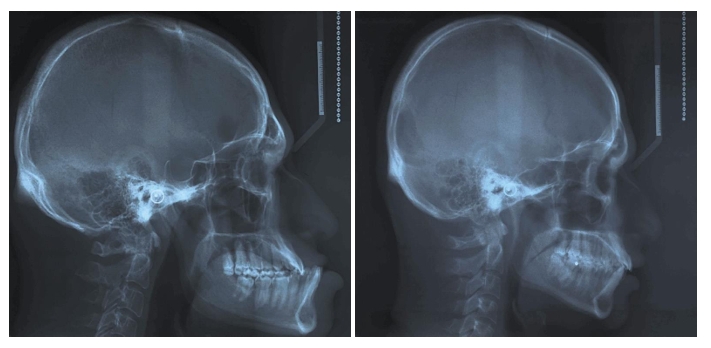

در یک پژوهش جالب، پزشکان چهرهی یک مرد مبتلا به آکرومگالی را با برادر دوقلوی سالمش مقایسه کردند تا مشخص شود این بیماری دقیقا چه تغییراتی در صورت ایجاد میکند. نتایج بررسی:

- در بیمار آکرومگالی، فک پایین بزرگتر و جلوتر از حالت طبیعی بود.

- فک بالا و بینی هم کمی جلوتر آمده بودند، اما تغییرشان کمتر بود.

- قسمتهایی مثل پیشانی، لبها و بینی ضخیمتر و برجستهتر دیده میشدند.

علت اصلی این تغییرات، افزایش هورمون رشد و IGF-1 است که باعث تحریک رشد غضروف و استخوان میشود. نتیجه

آکرومگالی بهویژه روی فک پایین و استخوانهای صورت اثر میگذارد و باعث میشود چهره حالت برجسته و متفاوتی پیدا کند. درمان به موقع و کنترل سطح هورمون رشد میتواند از پیشرفت این تغییرات جلوگیری کند.

شکل 1 بیمار سمت چپ دارای آکرومگالی و بیمار سمت راست برادر دوقلوی سالم